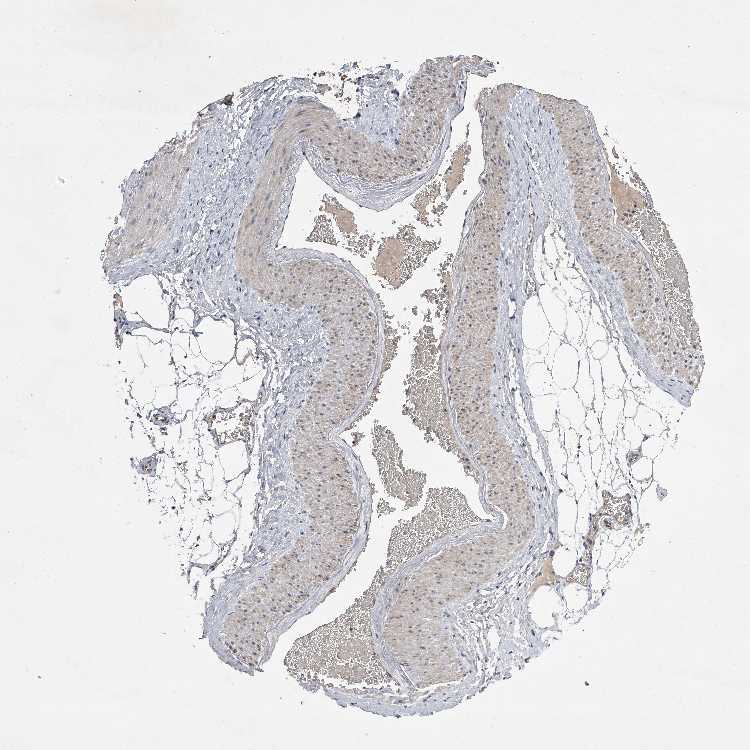

ADIPOSE TISSUE - Antibody stainingi

Antibody staining in the annotated cell types in the current human tissue is reported as not detected, low, medium, or high, based on conventional immunohistochemistry profiling in selected tissues. This score is based on the combination of the staining intensity and fraction of stained cells.

Each image is clickable and will lead to virtual microscopy that enables deeper exploration of all samples and also displays staining intensity scores, fraction scores and subcellular localization as well as patient and tissue information for each sample.

Antibody HPA030090Antibody HPA030091

Adipocytes LowNot detected